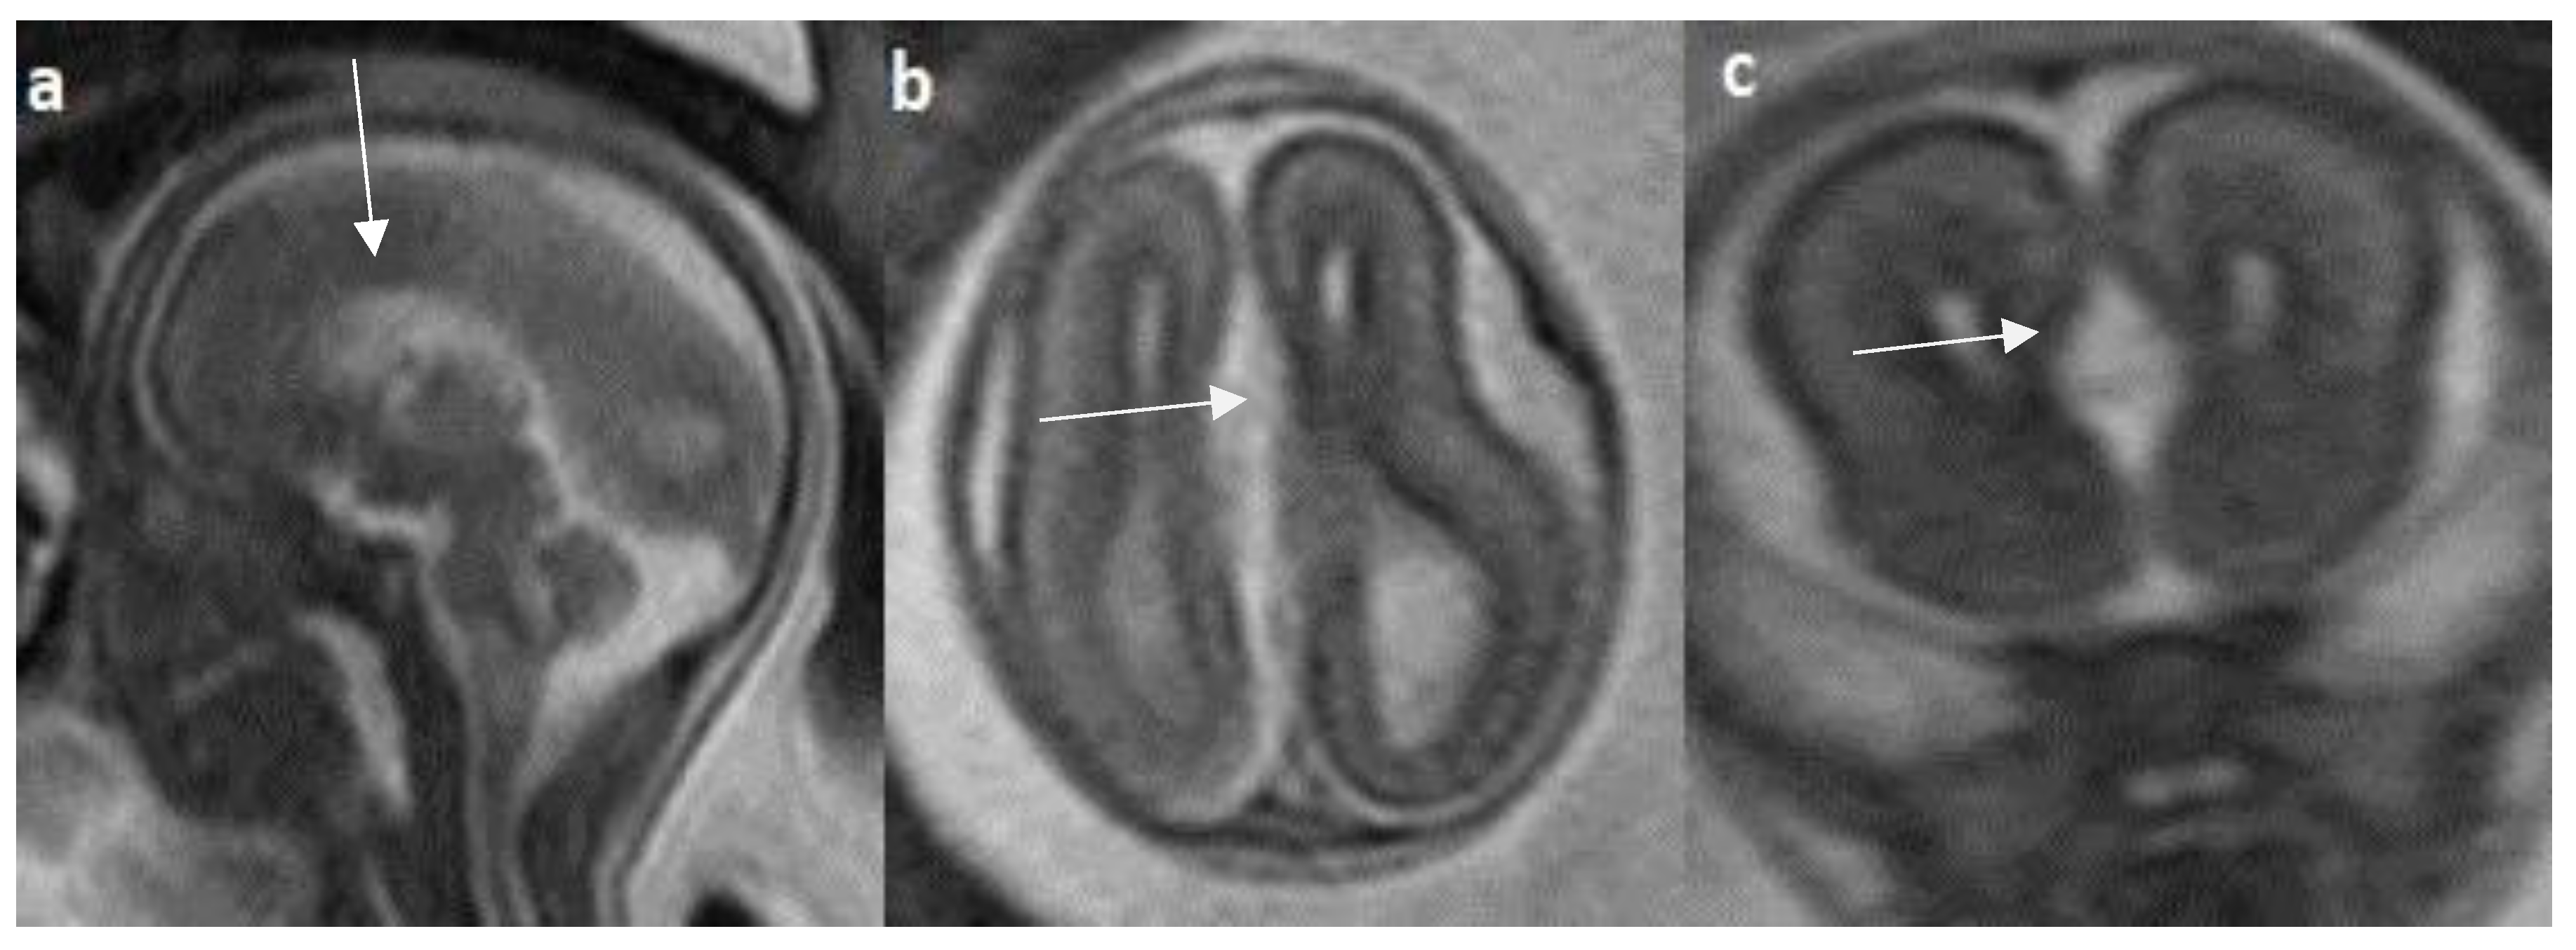

- Manor C, Rangasami R, Suresh I, Suresh S. Magnetic Resonance Imaging Findings in Fetal Corpus Callosal Developmental Abnormalities: A Pictorial Essay. J Pediatr Neurosci. 2020 Oct-Dec;15(4):352-357. [CrossRef]

- Hyun Yoo J, Hunter J. Imaging spectrum of pediatric corpus callosal pathology: a pictorial review. J Neuroimaging. 2013 Apr;23(2):281-95. [CrossRef]